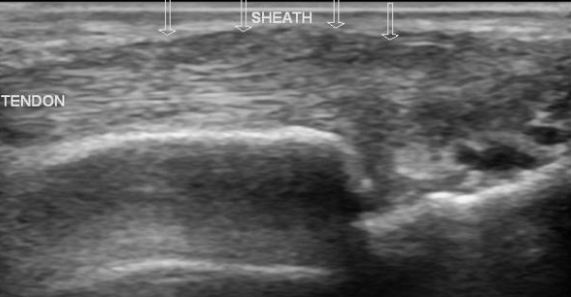

Tendinose et Ténosynovite

Ténosynovite du Tunnel Carpien